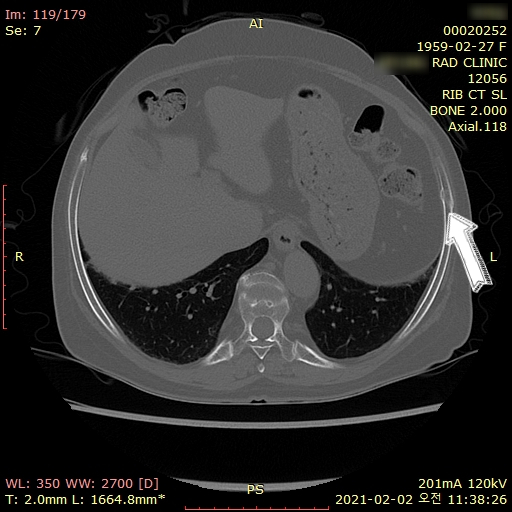

위 환자분은

골절이 강력하게 의심되어

협력의원으로 즉시 전원하여

검사한 결과

급성 골절로

진단받으셨구요.

화살표 친 부위에

오래 전 과거에 이미 골절되어

가골이 형성된 부분도

확인할 수 있었습니다.

2-3주가 지나면

가골이 형성되어

오래된 골절인지

급성 골절인지

영상검사만으로

감별하기 쉽지 않습니다.